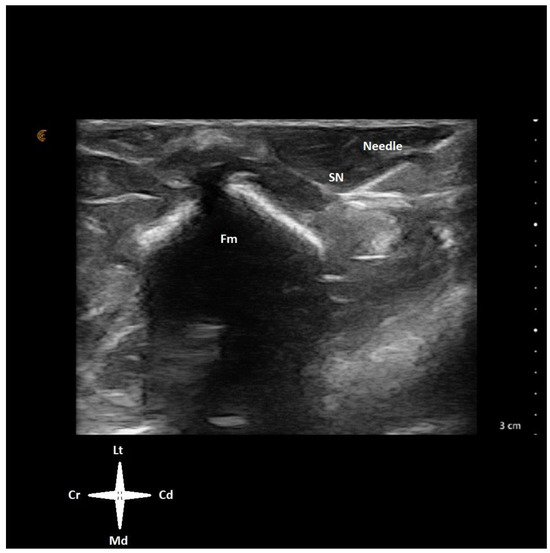

An ultrasound-guided sciatic nerve block was performed as part of the analgesic protocol using a 22 G, 50 mm Quincke needle (Sonoplex®STIM, Pajunk, Geisingen, Germany) and a linear ultrasound probe (L7VET, Clarius, Vancouver, BC, Canada). The relevant anatomical structures and the sciatic nerve were localised using the technique already described in other avian species [2]. The probe was placed on the lateral side of the thigh in a transverse orientation to the long axis of the limb at mid-distance between the hip and the knee (Figure 1). Both components of the sciatic nerve, the common peroneal and tibial nerve, were identified caudal to mid-femur between the lateral and medial muscles of the thigh (iliotibialis lateralis and iliofibularis flexor cruris lateralis on the lateral side, and flexor cruris medialis and femurotibialis internus on the medial side) [8]. The needle was advanced in-plane through the caudal aspect of the thigh and advanced in a caudo-cranial, latero-medial direction, aiming to reach the sciatic nerve proximity (Figure 2). Levobupivacaine 1 mg/kg (Levobupivacaine 0.5 mg/mL, Fresenius Kabi, Huis Ter Heide, Netherlands Nederland) was injected around the nerve through the prefilled needle using a 2 mL volume syringe. Prior to local anaesthetic injection, a negative aspiration test was performed to confirm extravascular needle placement. No resistance to the injection was felt. The sonographic image confirmed the sciatic nerve was embedded in the local anaesthetic solution (Video S1). Intraoperative nociception was considered when the heart rate and respiratory rate increased sharply by 20% of the baseline values in response to a surgical stimulation. Ketamine 0.5 mg/kg was prepared as a rescue systemic analgesic drug.

Figure 2. Ultrasound window of the left pelvic limb of a juvenile emu positioned in right lateral recumbency. The transducer was placed on the lateral side of the thigh in a transverse orientation to the long axis of the limb at mid distance between the hip and the knee. An insulated needle was advanced in-plane in a cranio-medial direction aiming for the proximity of the sciatic nerve (SN). Cr—cranial, Cd—caudal, Lt—lateral, Md—medial, Fm—femur.